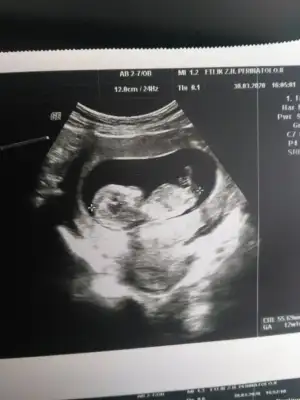

14 haftalık tahmin izi alabilirmiyim

Eklentiler

• 20200325_142938.webp

20200325_142938.webp

10,9 KB · Görüntüleme: 68

• 20200325_142911.webp

20200325_142911.webp

11,9 KB · Görüntüleme: 87